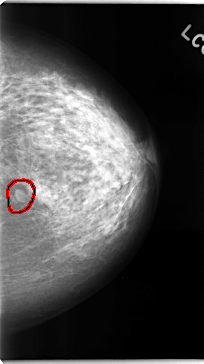

C_0102_1.LEFT_CC

LEFT_CC LINES 4728 PIXELS_PER_LINE 2640 BITS_PER_PIXEL 12 RESOLUTION 50 OVERLAY

FILE: C_0102_1.LEFT_CC.OVERLAY

TOTAL_ABNORMALITIES 1

ABNORMALITY 1

LESION_TYPE MASS SHAPE OVAL MARGINS CIRCUMSCRIBED

ASSESSMENT 3

SUBTLETY 5

PATHOLOGY BENIGN

TOTAL_OUTLINES 1

BOUNDARY